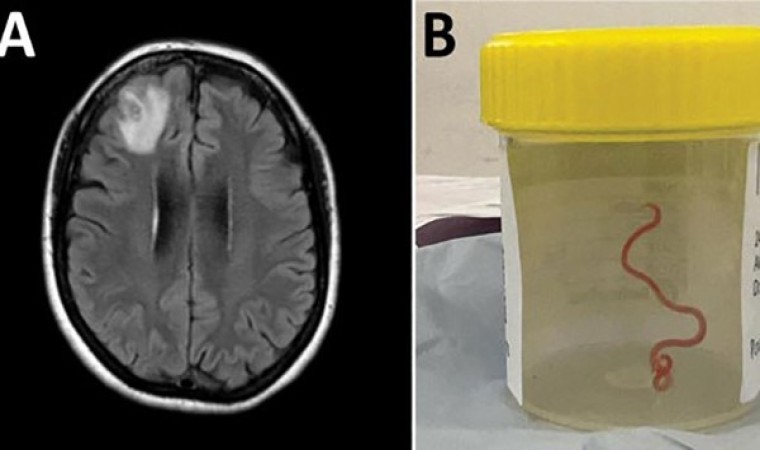

Avustralya Ulusal Üniversitesi’nden (ANU) yapılan açıklamaya göre 64 yaşındaki bir kadın karın ağrısı, ishal, kuru öksürük, ateş ve geceleri terleme şikayetleriyle ilk olarak Ocak 2021’in sonlarında hastaneye kaldırıldı. Daha sonra 2022 yılında unutkanlık ve depresyon şikayetleri de görülen kadın, Canberra Hastanesi’ne sevk edildi. MR taraması yapılan kadının, beyninin sağ ön lobunda anormallik tespit edilmesi üzerine ameliyat kararı verildi. Ameliyat sırasında doktorlar, kadının beyninde 8 santimetre uzunluğunda canlı solucan buldu. Latince adı "Ophidascaris robertsi" olan solucanın normalde piton yılanlarında bulunan bir parazit olduğu belirtildi. ANU ve Canberra Hastanesi’nin önde gelen bulaşıcı hastalık uzmanı Doçent Sanjaya Senanayake, “Bu, dünyada bir insanda görülen ile Ophidascaris vakasıdır” ifadesini kullandı.

Kadının evinin yakınlarında bir göl olduğu, gölün çevresinde de söz konusu parazitin yaşadığı piton türünün bulunduğu ifade edildi. Pitonun paraziti boşaltım yoluyla attığı, kadının ise gölün yanında bulunan yeşilliklere dokunması ya da topladığı yeşillikleri yemekte kullanması sonucu paraziti vücuduna aldığı belirtildi.